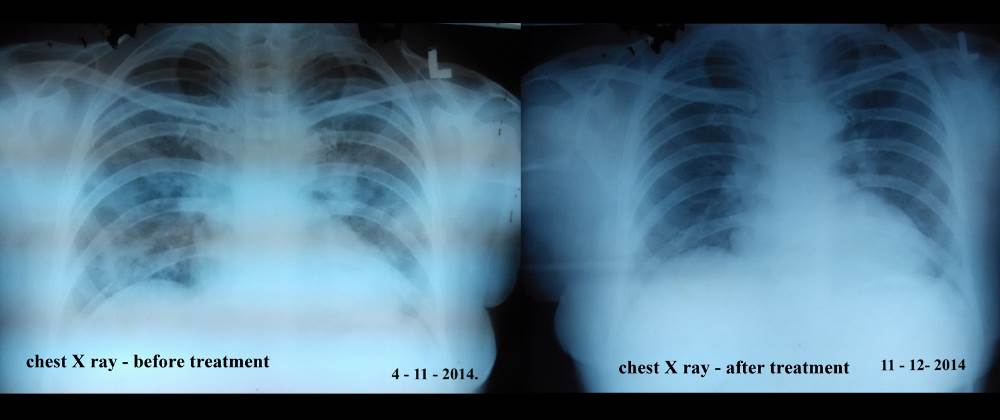

On the day of admission patient’s general examination showed pallor, mild edema on limbs and chest crackles. Objective evidences include elevated erythrocyte sedimentation rate (ESR) (54 mm/1st hr) and slightly elevated eosinophils. Peripheral capillary oxygen saturation (SPO2) was dropped to 90% and chest X ray showed bilateral infilterate and the white patches on both lungs. Pulmonologist treated her symptomatically with bronchodilators, mucolytics and antibiotics, but the symptoms persisted. On third day sputum acid fast bacilli (AFB) results obtained and it was negative. On day 4 HRCT scan done which reveals patchy areas of ground glass opacities with smooth intralobular septal thickening and intralobular interstitial thickening (crazy pavement appearance). It also showed areas of central ground glass opacities with denser consolidation in both lungs and confirmed the diagnosis as BOOP. The patient was asked to discontinue all the ayurvedic medicines and steroid therapy with IV PREDNISONONE 40 mg OD was started on the day 4. After 5 d of therapy, as the symptoms improved IV PREDNISOLONE 40 mg replaced with oral prednisolone 16 mg OD for 2 d. During treatment patient was also administered with conventional antibiotics-AZITHROMYCIN 500 mg OD for 5 d and LEVOFLOXACIN for next 5 d. On day 10, patient symptomatically improved and saturation increased to 97%. Patient got discharged with oral steroid (PREDNISOLONE 8 mg 1-0-0) for 2 w and advised to discontinue ayurvedic treatment for RA.

Fig. 2: Chest X ray before and after treatment

Patient discontinued the ayurvedic medications and restarted allopathic medication for arthritis. Rheumatologist advised her to restart Tab. HYDROCHLOROQUINE 200 mg OD and tab AZATHIOPRIM BD and suggested review in clinic after 1 mo. After 2 w, patient reviewed in pulmonary outpatient department. She appeared to be symptomatically better and respiratory manifestations suppressed. Tab. PREDNISOLONE dose tapered from 8 mg to 4 mg OD and advised to review after 2 w with chest X ray.

On her second review, her chest X ray was clear without infiltrations. Her steroid dose is tapered to Tab. PREDNISOLONE 2 mg OD for 2 w and 2 mg OD on alternate days for next 2 w. She continued her arthritis medications along with prednisolone and reviewed after 4 w.